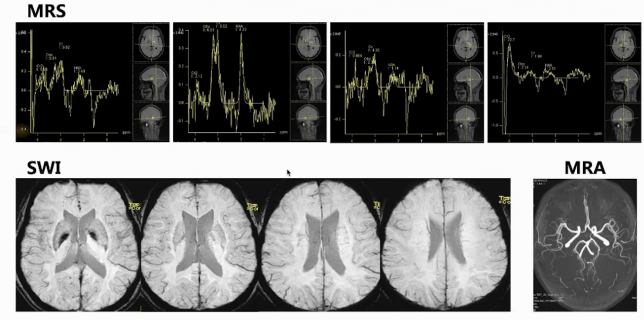

颅脑磁共振:双侧基底节区、放射冠区域片状长T2高信号,累积部位深,无显著占位效应,呈长T1长T2信号。增强后,仅见小斑片状轻度强化影,左侧基底节区及放射冠区域较明显,脑岛区无明显异常强化。DWI信号增高,部分区域ADC信号减低,提示弥散受限。多体素MR波谱扫描多数区域胆碱峰升高,部分体素N - 乙酰天门冬氨酸峰降低。SWI和颅脑MRA扫描未见明显微出血及血管异常。颅脑灌注加权成像显示病灶区域脑血流量CBF、脑血容量CBV轻度升高,达峰时间TTP及平均通过时间MTT稍延迟。

总结:中年女性,病灶大致对称分布,双侧深部区域受累为主,有明显弥散受限,波谱扫描Cho峰升高,血管检查无异常。